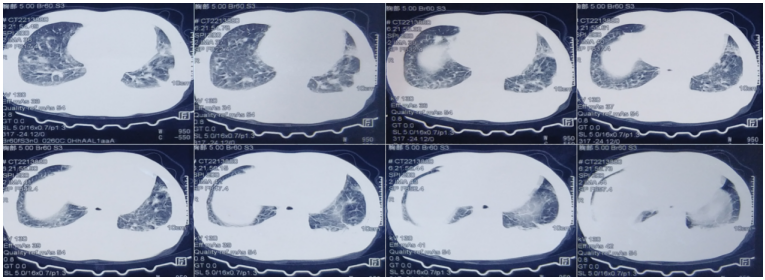

• 胸部CT:双肺渗出性病变,双侧胸腔积液(图1)

1  患者胸部CT(2022-04-18)

2022年4月25日(D7),患者尿量恢复,撤离CRRT。4月26日(D8),撤机拔管,序贯高流量氧疗。4月27日复查胸部HRCT示:病灶较前明显吸收(图15)4月30日(D12),病情好转出院。嘱托:口服复方磺胺甲噁唑0.96 g q8h维持治疗1年。

15  复查胸部HRCT(2022-04-27)